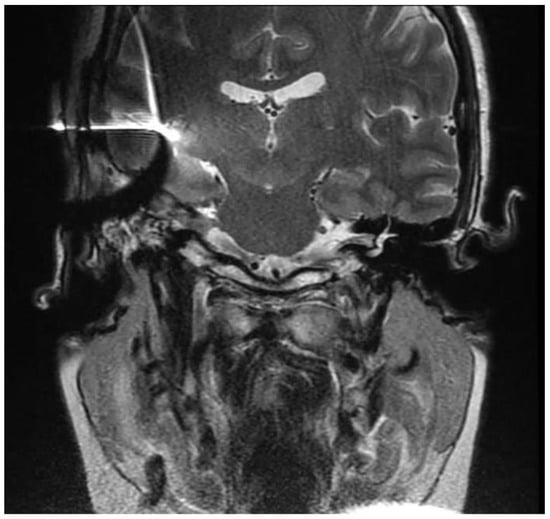

2. Case Report